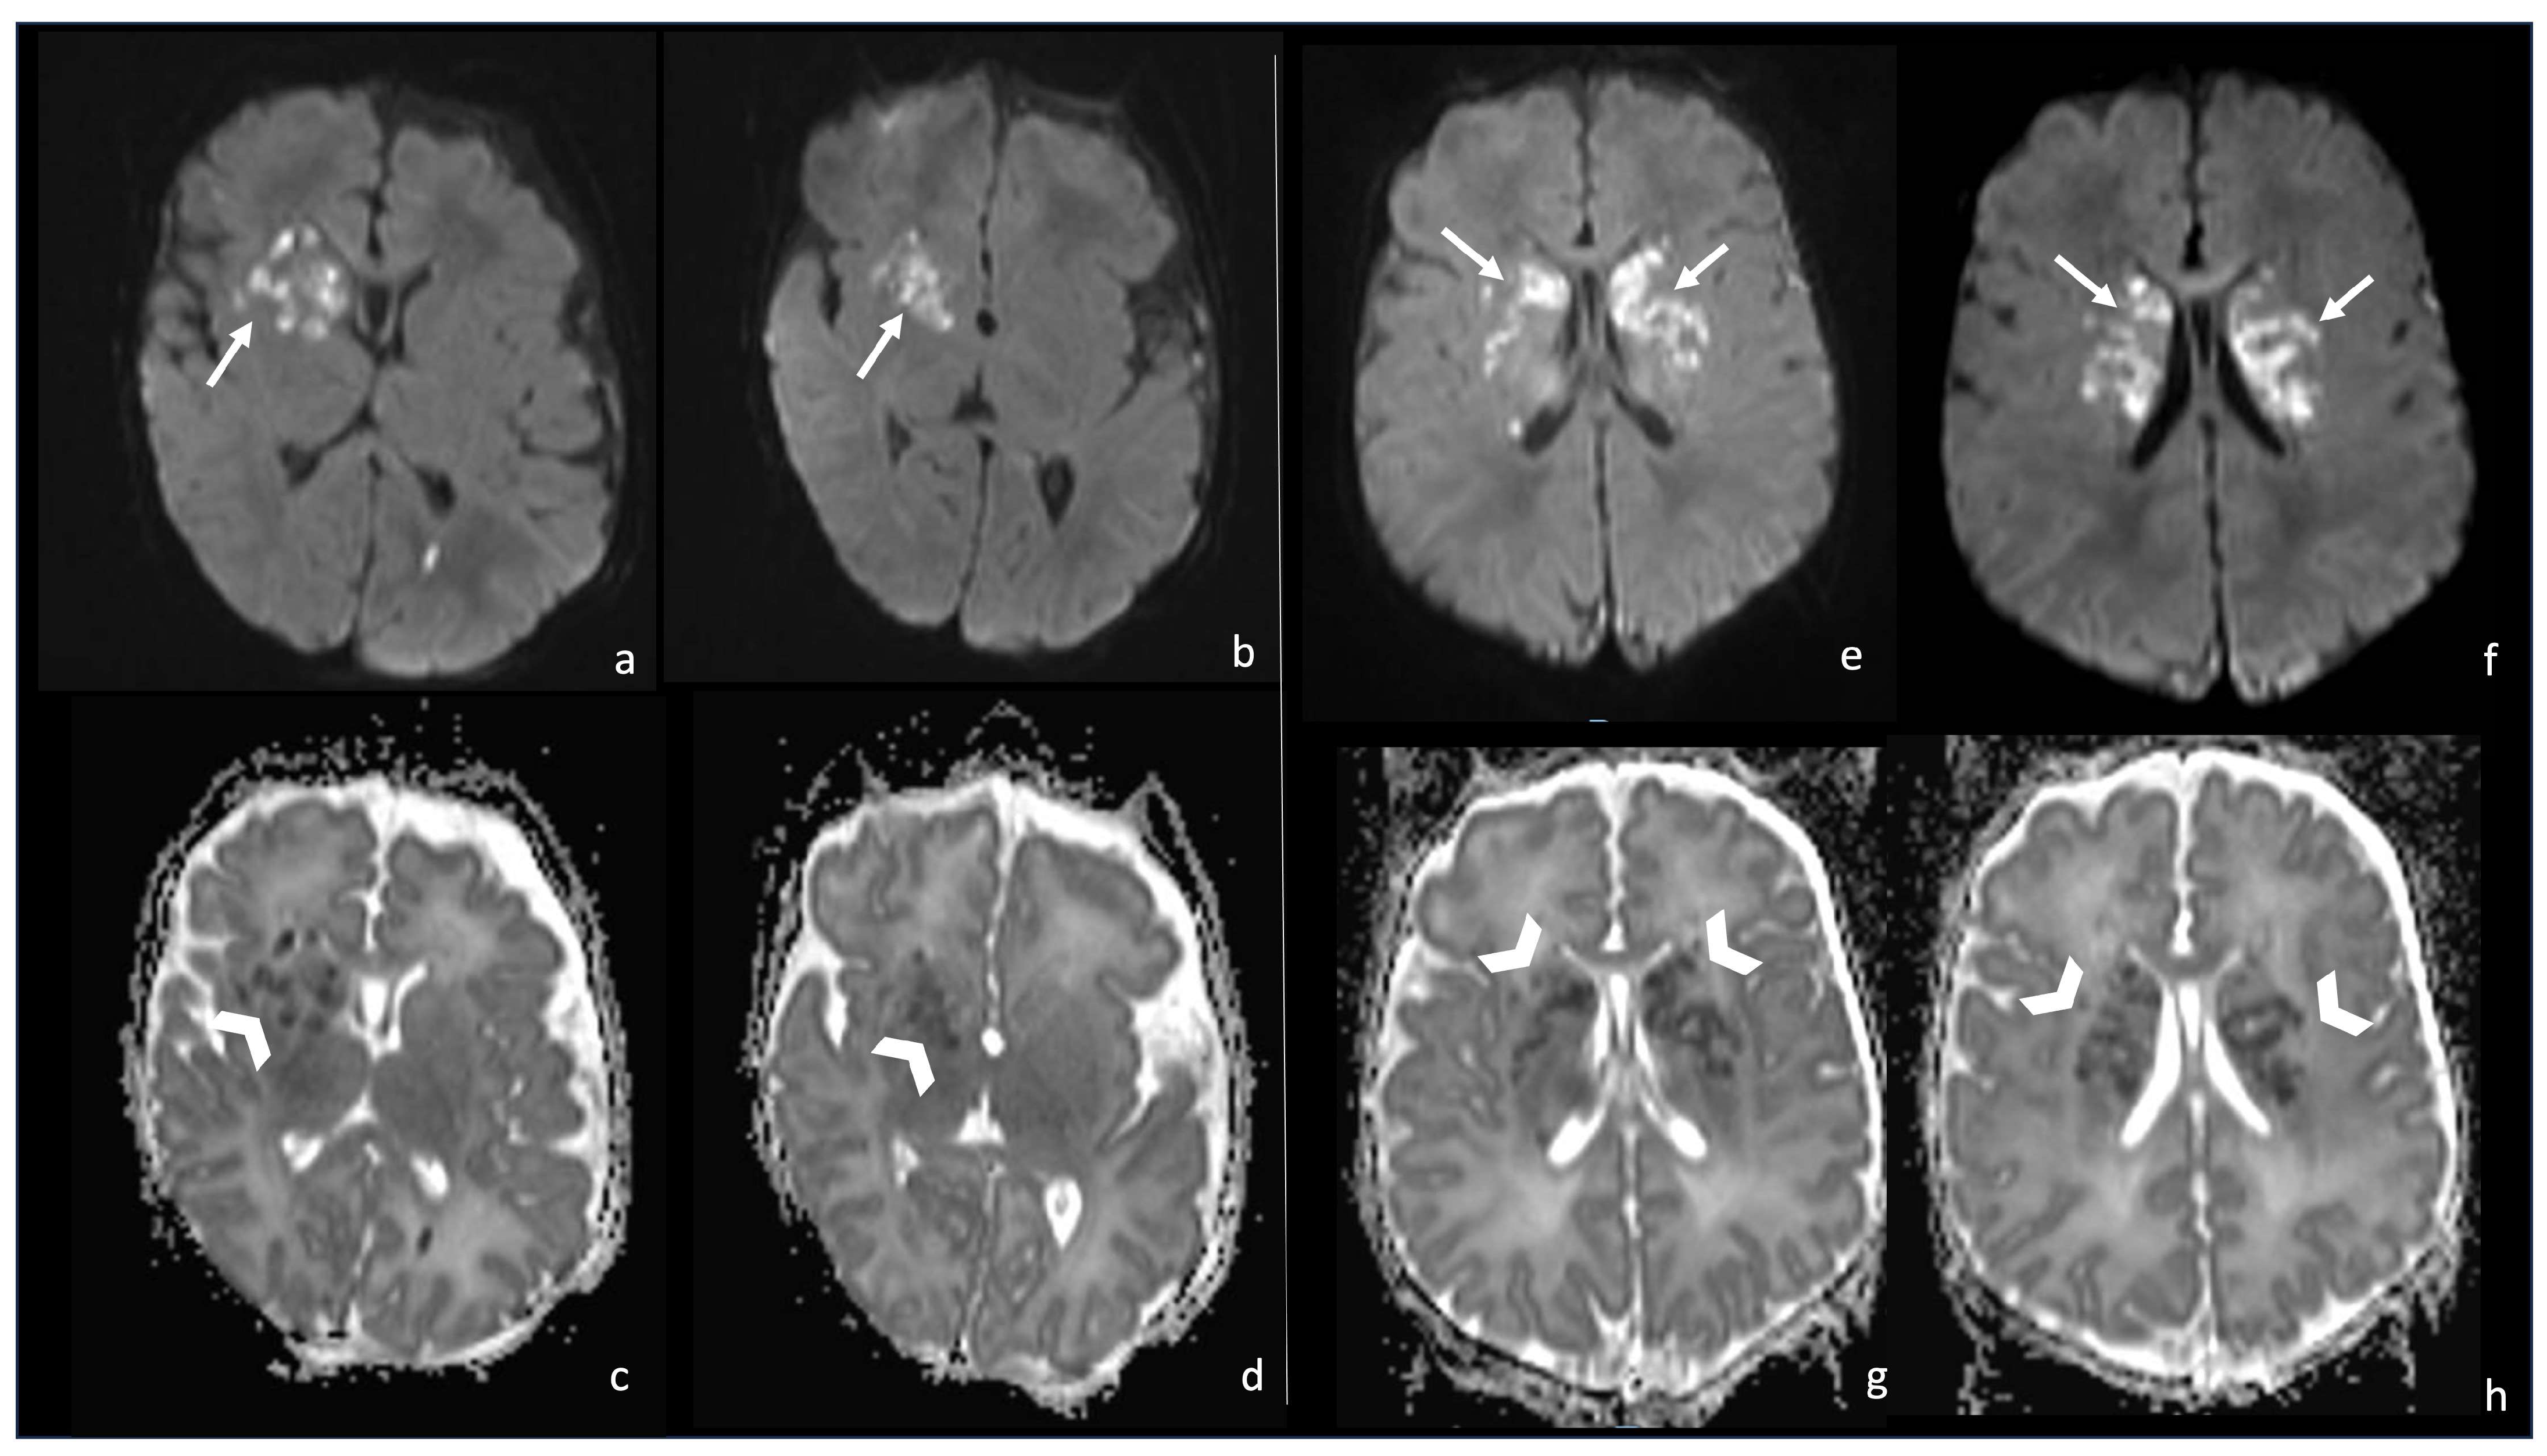

7.1. Group B Streptococcus

7.2. Listeria Monocytogenes

7.3. Gram-Negative Bacteria and Abscesses